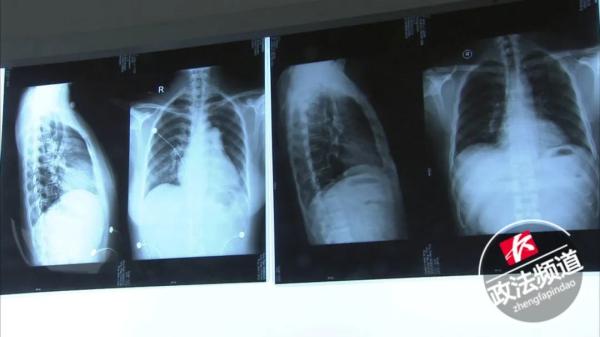

在医院的检查结果中发现:

钟女士的心脏比正常人大3倍。